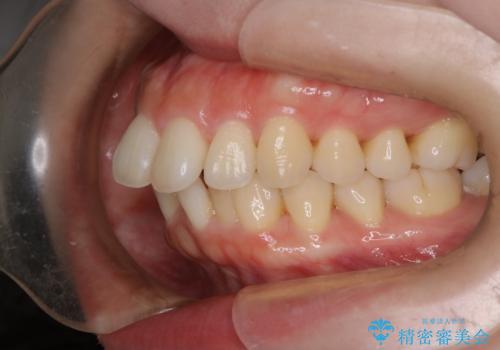

【審美装置】癒合歯がある方の治療

- 前歯の前突を主訴に来院されました。

下の前歯は癒合歯がある珍しいケースです。

治療に関しては小臼歯を4本抜歯して前歯を下げるような計画を立てて治療しました。

抜歯スペースの移動量を調整するために、矯正用アンカースクリューや親知らずを活用して治療を行いました。